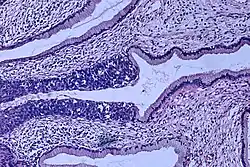

Invasive squamous cell carcinoma of the cervix is characterized by infiltration as irregular anastomosing nests or single cells.[75] This case is poorly differentiated. H&E stain. -

Cervical squamous cell carcinoma generally shows diffuse staining of both nuclei and cytoplasm on p16 immuno-

histochemistry (except verrucous variant).[76] -